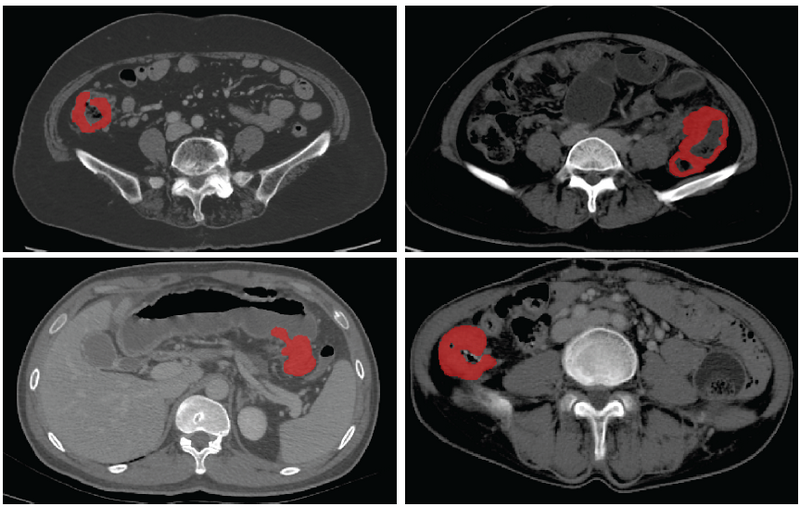

基于CT影像的結(jié)腸癌病灶分割

據(jù)介紹,基于醫(yī)學影像的人工智能為腸癌個體化診療提供了巨大的可能性,已經(jīng)有多項研究實現(xiàn)了病人的療效預測、術(shù)后復發(fā)風險評估,但這些應用無不依賴于精準的病灶分割。此次SOUSA技術(shù)的開發(fā)在國際上首次實現(xiàn)了結(jié)腸癌的自動分割,為加速腸癌人工智能精準診療的臨床應用奠定了基礎(chǔ)。自動化標準化的精準影像信息處理將有效地降低經(jīng)濟、時間和人力成本,為精準診療的實施提供了重要的臨床依據(jù),具備極大的臨床轉(zhuǎn)化應用前景。

團隊利用來自中山大學附屬第六醫(yī)院和喀地一院的923例有標注結(jié)腸癌CT影像和2670例無標注結(jié)腸癌CT影像作為SOUSA框架的訓練數(shù)據(jù)集,并利用417例結(jié)腸癌CT影像對SOUSA框架進行驗證,結(jié)果顯示其自動分割效果優(yōu)于現(xiàn)有的弱監(jiān)督和半監(jiān)督學習模型。與目前最先進的方法ICT (Verma et al.,2019)、不確定性感知(Yu et al.,2019)和自我訓練相比,SOUSA框架在每個數(shù)據(jù)比率上都達到了最佳性能。此外,當數(shù)據(jù)集的大小有限時,SOUSA框架的性能甚至與使用密集注釋的模型的性能相當。